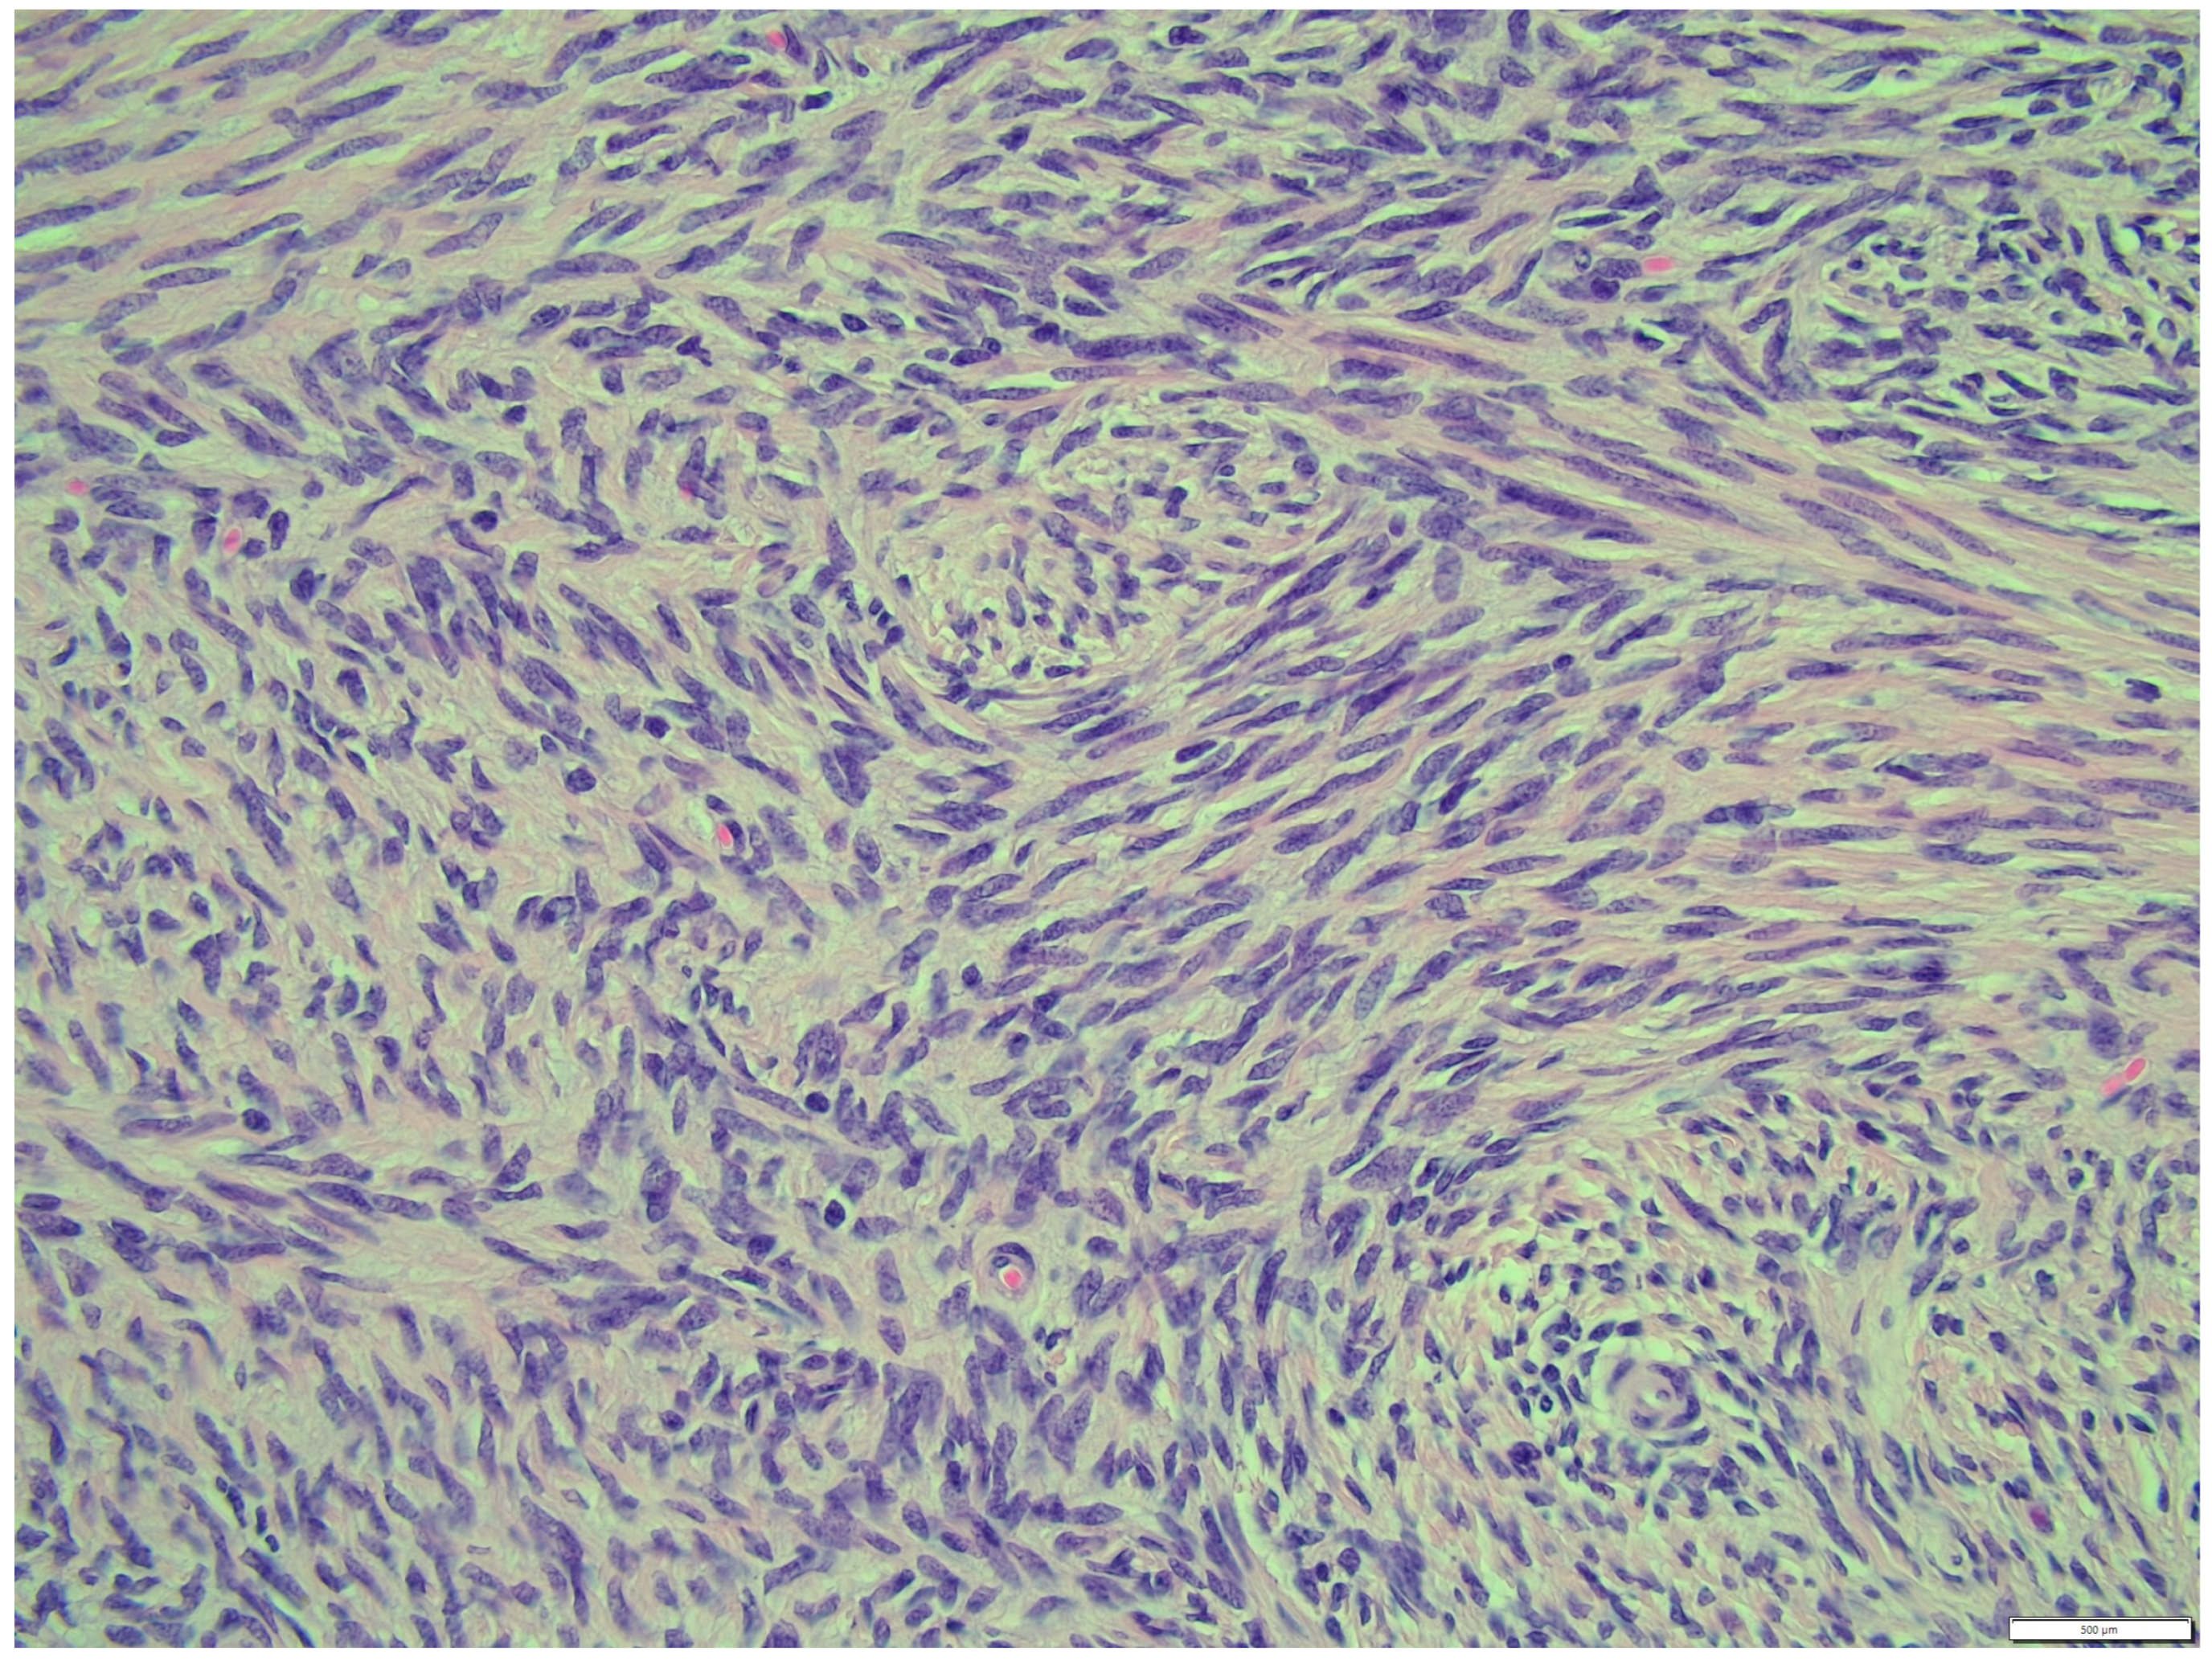

The fibroma was composed of uniform medium-sized, spindle-shaped cells with indistinct borders and a regularly shaped and sized oval, dark or gray nucleus to long thin nucleus cells. The indistinct nucleoli and finely stippled chromatin in the nucleus were observed. The nucleus/cytoplasm ratio favored the cytoplasm. The cytoplasm was pink and long, as is common in mature spindle cells. Spindle cell anisocytosis and anisokaryosis were mild to moderate (Figure 14). Mitoses were typical. The rate of mitoses was low—2 per 10 fields at 400 magnification. The spindle-like cells were arranged in sweeping fascicles angled in a chevron-like or herringbone pattern (Figure 15). In addition, storiform areas were observed (Figure 16). The stroma had a delicate intercellular network of collagen, but a few areas of “keloid-like” sclerosis/hyalinization were found (Figure 17). The histological pattern is typical for fibrosarcoma, but not for fibroma. However, tumor cells lacked marked atypia. The ovary-derived fibroma was considered to be a pure stromal tumor of the ovary.

Figure 15. The spindle like cells were arranged in sweeping fascicles that are angled in a chevron-like or herringbone pattern, fibroma part. HE, 200× magnification.

Animals 14 01307 g015